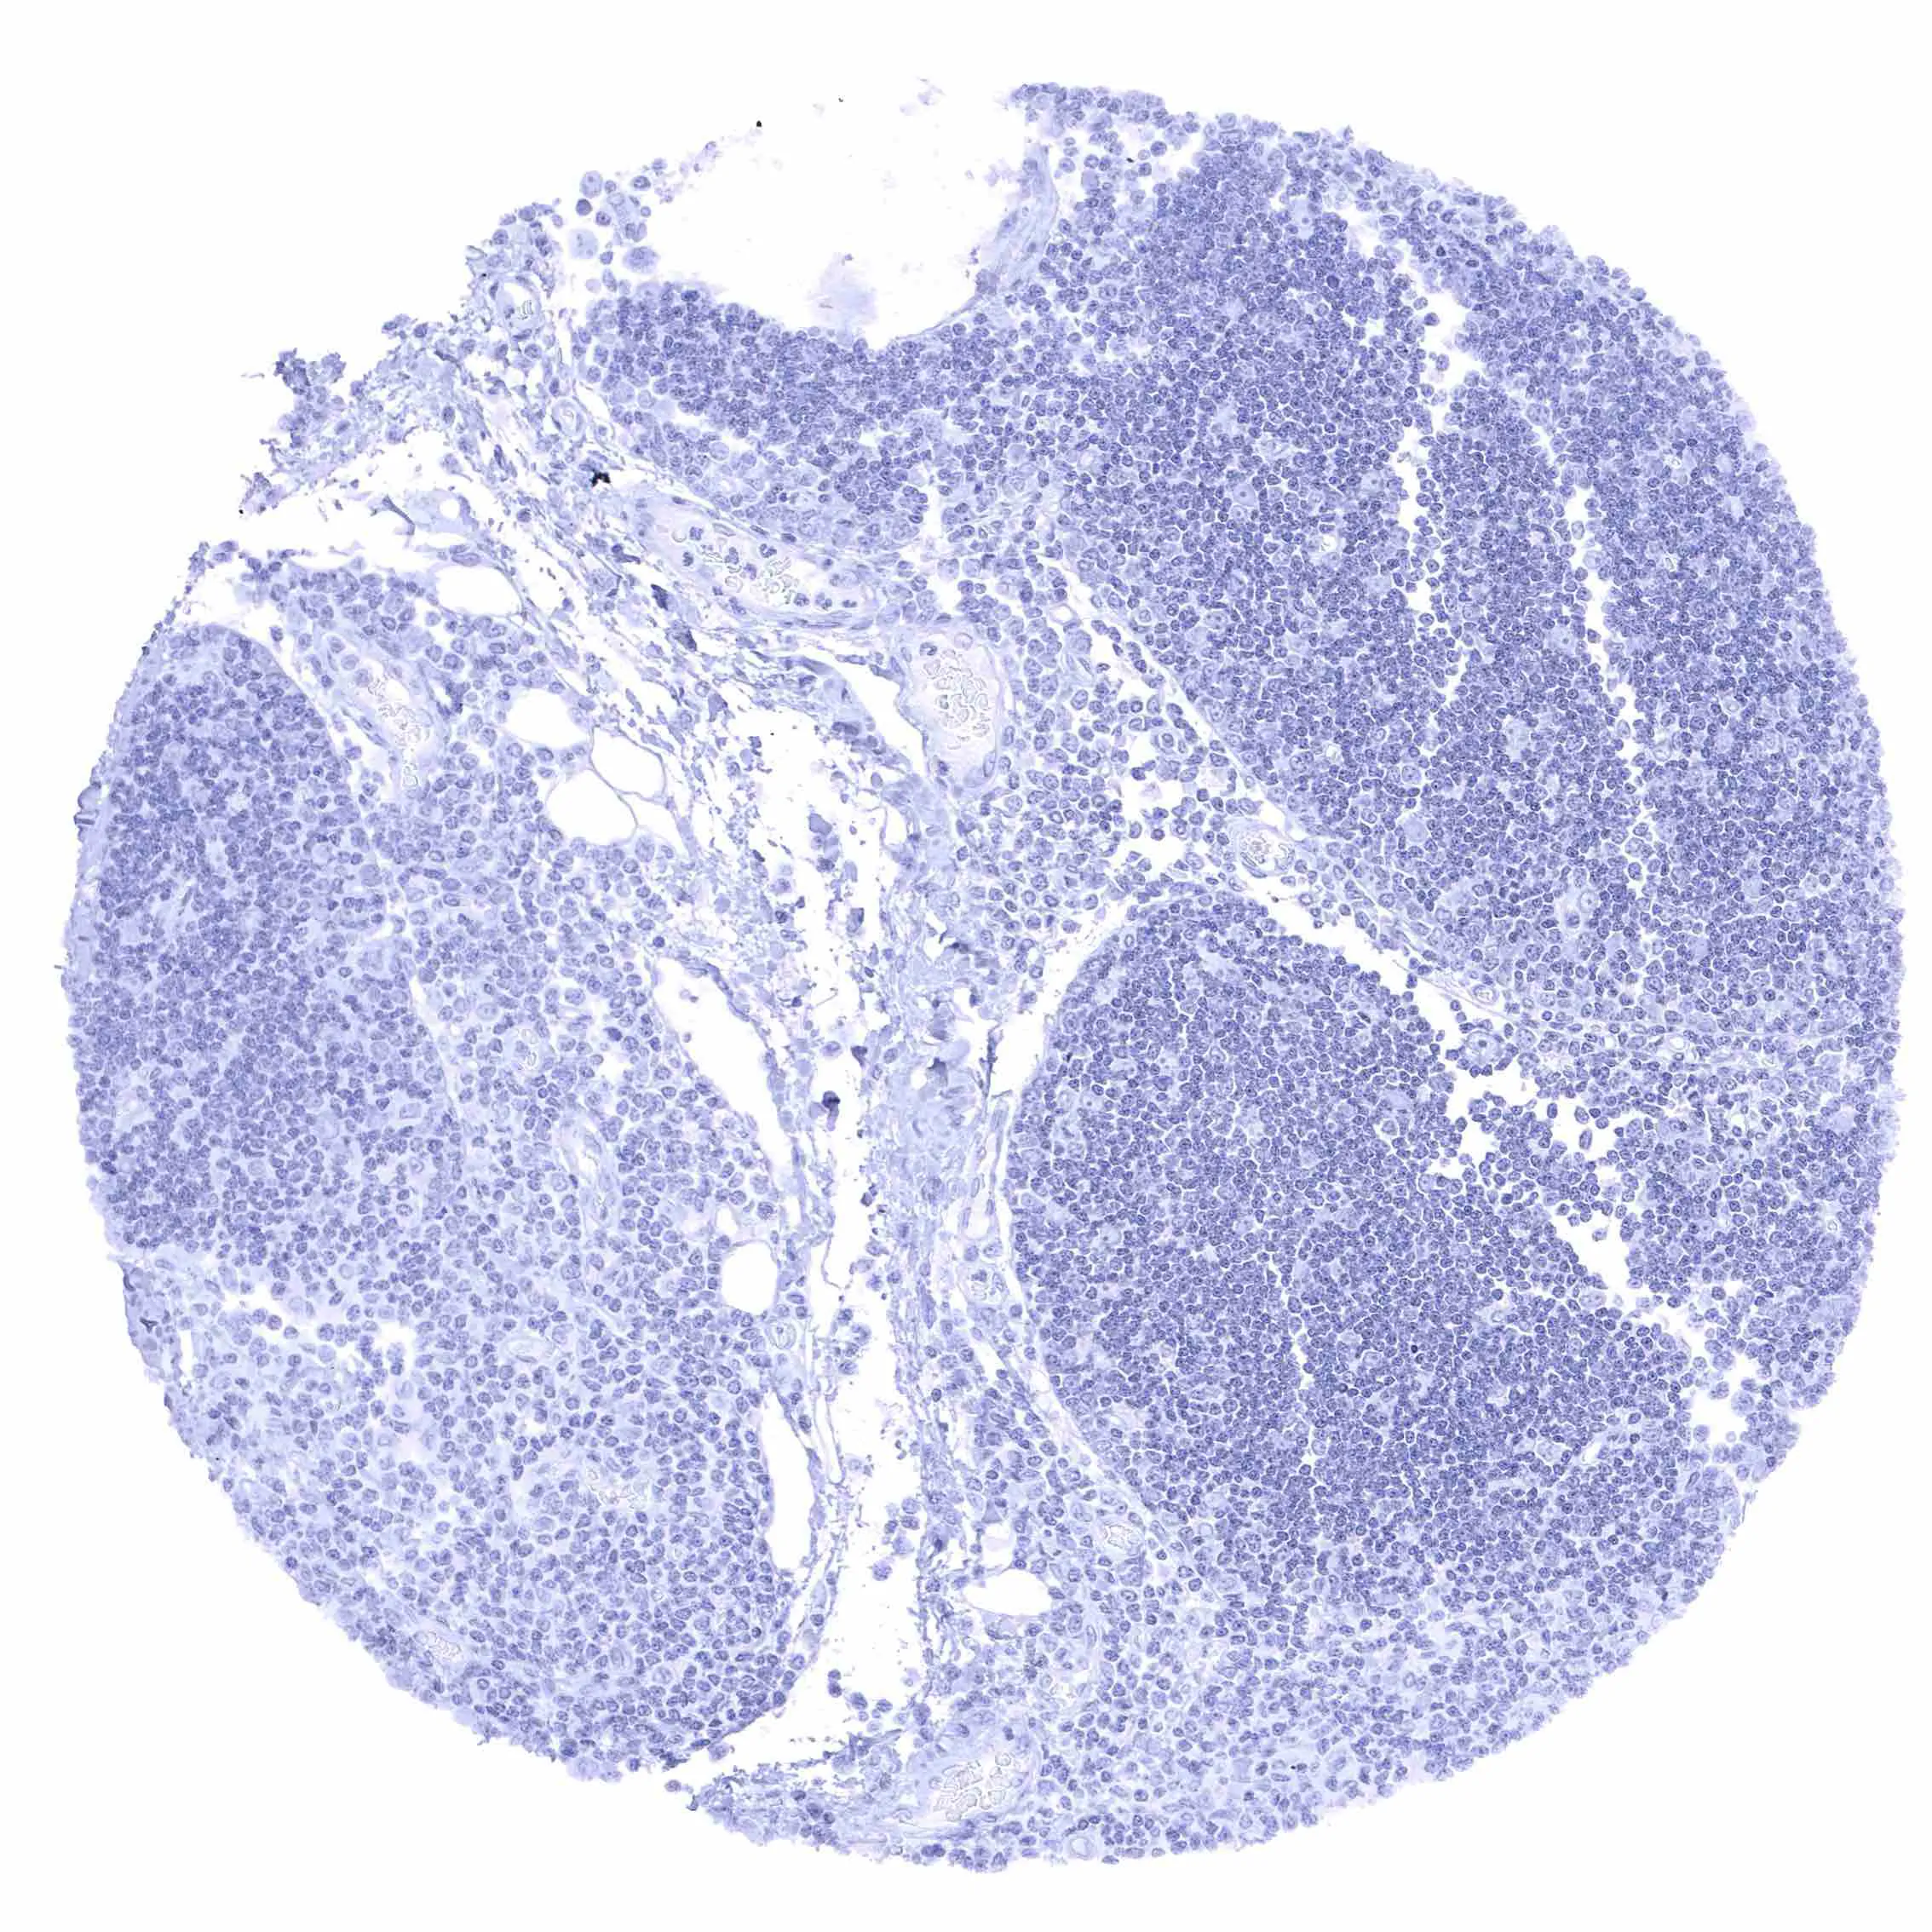

Lymph node